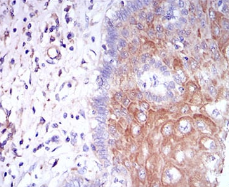

CSF1R Mouse Monoclonal antibody[6B9B9]

IHC    1/200 - 1/1000